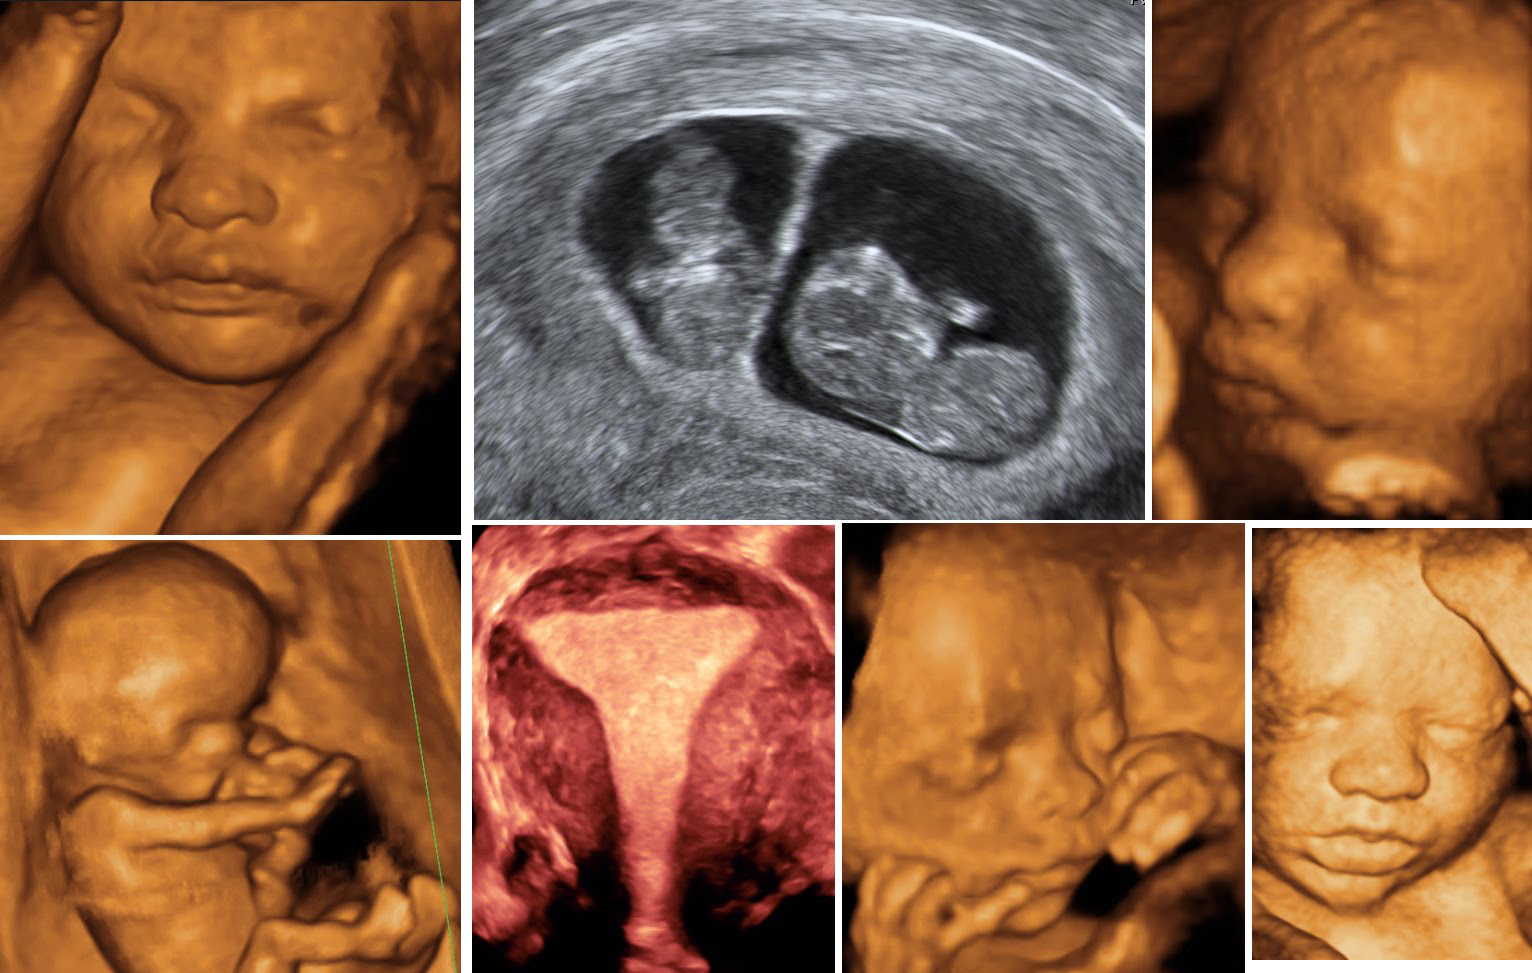

The Obstetric Color Doppler is a specialized ultrasound technique that goes beyond the traditional black-and-white images of the fetus. It visualizes blood flow in the umbilical cord, placenta, and baby's heart, providing vital information about the baby's health that standard ultrasounds might miss.

This is where the Obstetric Color Doppler shines. It helps expectant mothers like Meera gain a comprehensive understanding of their baby's development, allowing doctors to detect issues such as restricted blood flow or placental problems early on. Early detection means timely intervention, which can prevent complications and ensure a healthier pregnancy.

Empowerment and accessibility are crucial in the journey of every expectant mother, and the Obstetric Color Doppler offers both. It provides a window into the womb, a chance to witness the miracle of life while ensuring the baby's well-being. The reassurance it offers extends beyond the mother, touching the entire family, friends, and community.

For Meera and Rajesh, the journey through pregnancy was no longer clouded by uncertainty. With each Doppler session, they felt more connected to their baby, marveling at the tiny heartbeat they could see and hear. This emotional connection transformed their experience, turning apprehension into anticipation.